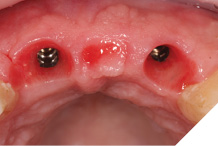

The definitive bridge was fitted and torqued in situ uneventfully after such excellent healing of the provisional bridge (Figs. 31-37).

Fig. 31

Fig. 32